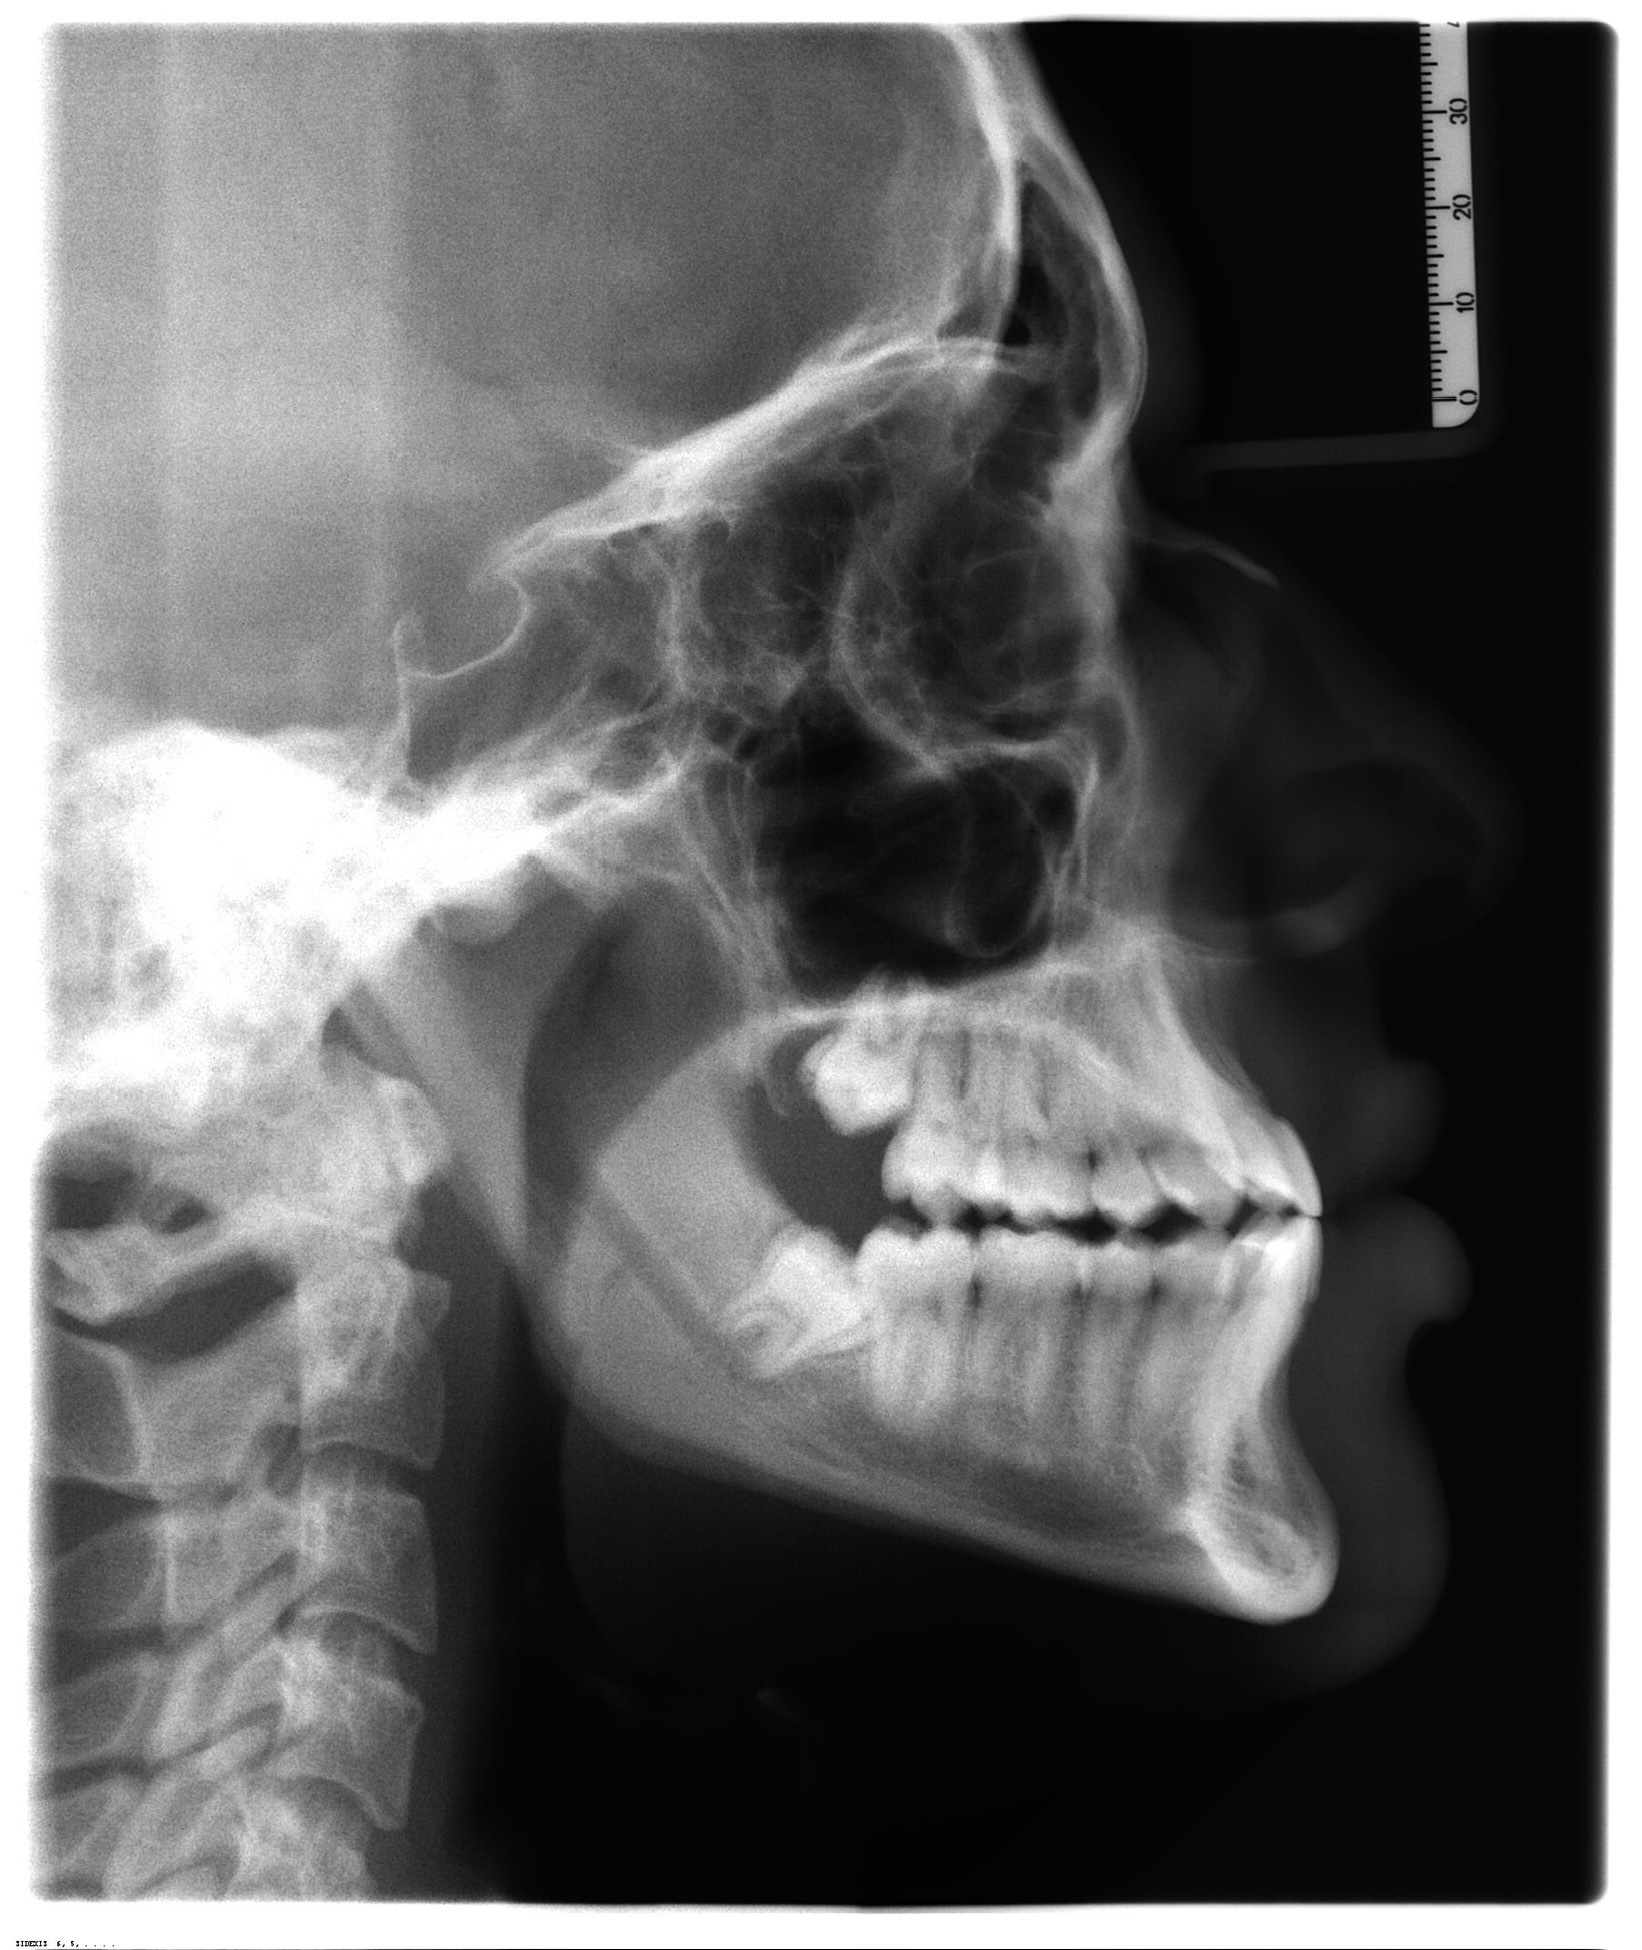

Could someone analysis my face and give me some advice maspe is planned open for double jaw surgery

you were always recessedCould someone analysis my face and give me some advice maspe is planned open for double jaw surgery

View attachment 4594873